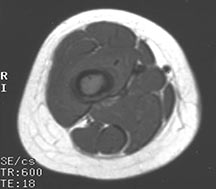

- May arise from any bone and any site within a bone (epiphyseal, metaphyseal, diaphyseal)

- Radiographically variable appearance: may appear benign (geographic) or malignant (permeative or moth eaten)